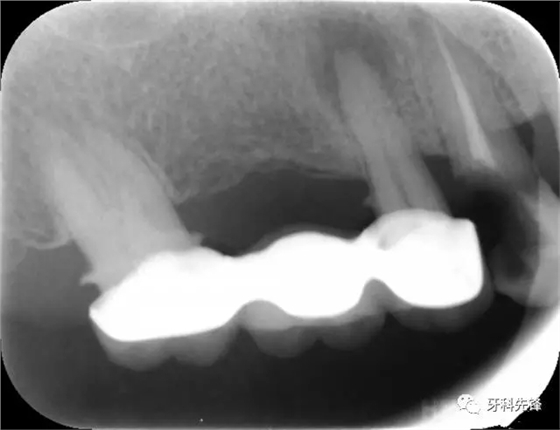

圖1術(shù)前X光片

X 示:15 根管透射,根尖有陰影

14根管阻射,恰填,無異常

46 根管阻射,恰填,根分叉骨密度降低,近中根尖陰影較大